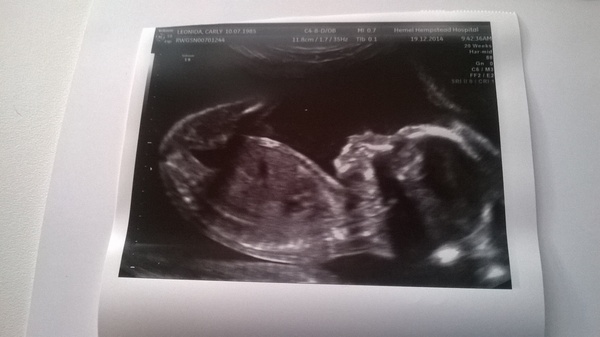

Justyouwaitandsee · 10/12/2014 19:54

Hello! Yes! We had the scan this morning Smile Here is the picture! Not much to report - all very quick and straightforward. Everything present and correct and where it should be. Although I brought up all the water which I'd forced myself to drink in the car park Sad

Didn't find out the sex but have a feeling it might be a girl. What do you ladies think?!

That looks like a girl to me justyouwait! Can't believe you are 20 weeks already! And that is a proper baby you've got in there!

Aw I'm so glad it went well justyouwait! It does look like a girl although I'm no expert. My bump looks a similar size to yours and I had to tell work yesterday as a few people had guessed (although they were v discreet) and the management team took it better than I expected. Ive got my scan a wk tomorrow, v excited. The baby has started kicking me a lot now, feels weird being poked at from the inside!